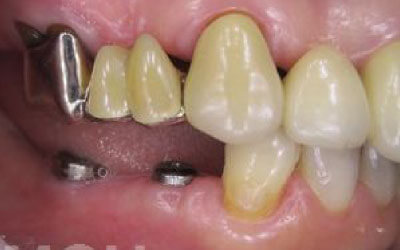

今回のご質問ですが、抜けた部分の骨が薄いなどの理由で「インプラントはできない」と言われた可能性があります。

前歯はもともと骨が薄く、歯が抜けると時間の経過とともにさらに骨が痩せてきてしまうので、インプラント治療の難易度が高い場所です。

ただ結論からお話すると、インプラント治療は可能です。

なぜなら、もし仮に骨が薄くても、骨の治療によって厚みが増せば、安全にインプラント治療が行えるからです。

なお、前歯のインプラント治療をご希望の方には、注意していただきたい点が4つほどあります。

また、インプラント治療においては、周囲の歯の状況や咬み合わせの問題などもしっかりと考えて治療するのがとても大切です。

そのため、残っている歯についてもきちんと診査してくれるクリニックが良いでしょう。